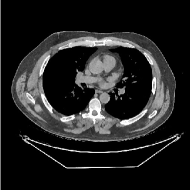

This section compares the generalization capabilities between the proposed MBIR method, PWLS-ST-, and a denoising deep NN, FBPConvNet [14], that are trained from the phantom data; in particular, we tested the trained PWLS-ST- and FBPConvNet models to phantom and clinical scan data. The results in Fig. 6 show that the non-MBIR FBPConvNet method has higher overfitting risks, compared to the proposed PWLS-ST- MBIR method. When tested on clinical scan data, PWLS-ST- achieves much more accurate reconstruction, compared to FBPConvNet. See Fig. 6(b). When tested on phantom data, FBPConvNet generates more unnatural features as the number of views reduces, although it gives lower RMSE values compared to PWLS-ST-. See zoom-ins in Fig. 6(a). The FBPConvNet results above correspond to those in the recent work [16] that FBPConvNet [14] generated some unexpected structures.

| FBPConvNet (Jin et al., 2017) | Proposed PWLS-ST- | Reference | |

| % () views | |||

| (a) XCAT phantom data | |||

| (b) GE clinical data | |||